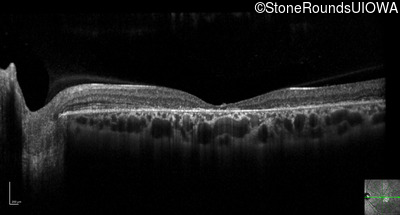

Optical Coherence Tomography - Right - 20/50 +2

Exemplar / OCT Stack